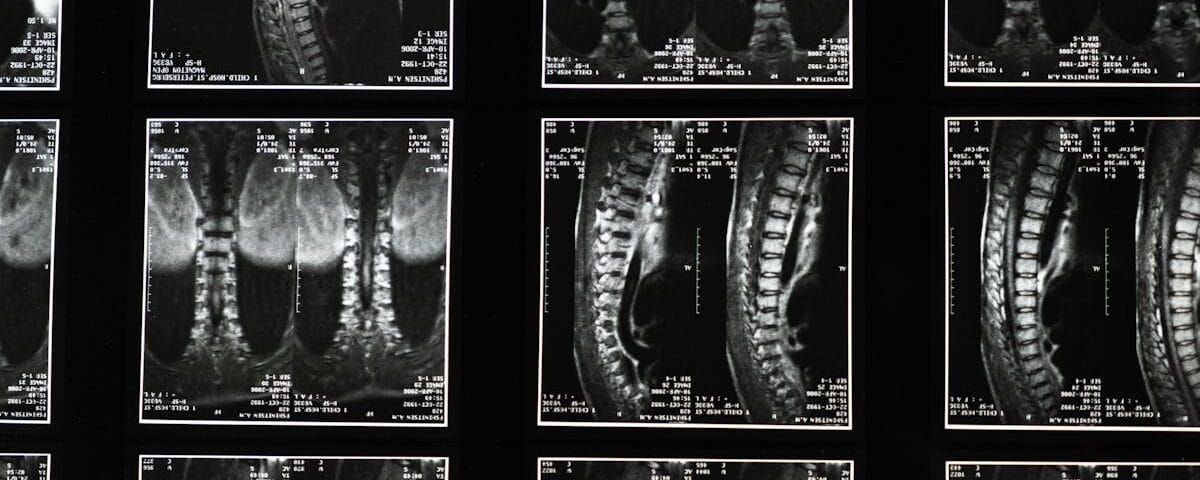

Sténose spinale et décompression neurovertébrale

Ce podcast décrit la sténose spinale, un rétrécissement du canal rachidien comprimant la moelle épinière ou les nerfs. Il détaille ses causes (dégénératives, structurelles, traumatiques, congénitales), symptômes […]